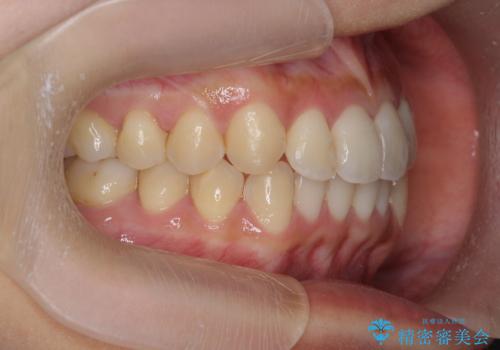

ワイヤー部分矯正治療を併用したマウスピース矯正治療

- 前歯のねじれ、深い噛み合わせ(ディープバイト)の改善を求めて来院されました。

マウスピースでは改善の難しい、歯のねじれ・ディープバイトを部分ワイヤー矯正で改善したのち、マウスピース矯正で全体の歯並びを整えていきます。

部分ワイヤー矯正を行ったことで前歯をしっかりと綺麗な歯並びへと導くことができました。